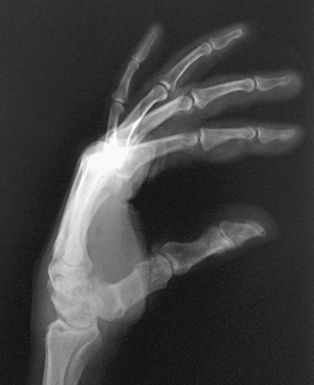

• Place the hand in its natural arched position with the palmar surface down and fingers flexed or resting on a sponge.

• Place the midline of the IR parallel with the long axis of the digit. Center the IR to the MCP joint.

• Adjust the arching of the hand until a true lateral position of the thumb is obtained (Fig. 4-39).

Structures shown: AP, PA, lateral, and PA oblique projections of the thumb are shown (Figs. 4-41 through 4-44).